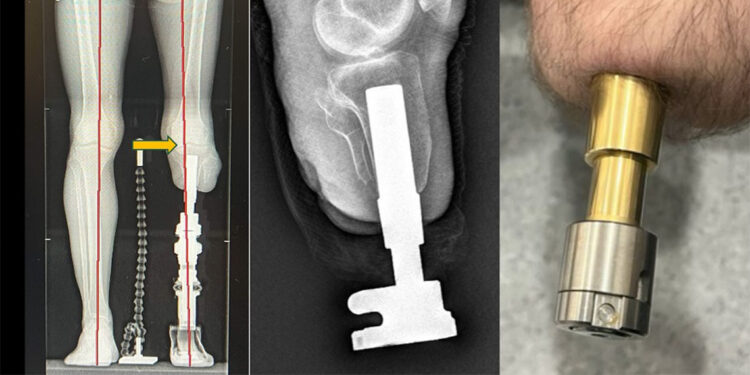

Osseointegrasyon yöntemi, soket protez kullanımında sorun yaşayan amputasyon hastalarına umut oluyor.

Ortopedi ve Travmatoloji Uzmanı Prof. Dr. Adnan Kara, “Kemiğe yerleştirilen implantlarla daha doğal ve konforlu bir yürüyüşü sunan bu yöntem Türkiye’de ilk kez kendi kurumlarımızda uygulandı” dedi.

Medipol Mega Üniversite Hastanesi’nden Ortopedi ve Travmatoloji Uzmanı Prof. Dr. Adnan Kara, “Bu yöntemle hastalar adeta kendi bacaklarıyla yürüme hissine kavuşuyor. Bu yöntemde, kemiğe yerleştirilen implant sayesinde yük doğrudan kemiğe aktarıldığından, çok daha doğal ve konforlu bir yürüyüş mümkün oluyor” diye konuştu.

Osseointegrasyon protezlerinin yapıldığı uzuvlar hakkında da bilgi veren Prof. Dr. Kara, yöntemin uyluk, kaval kemiği, dizüstü ve dizaltı gibi bölgelerin yanı sıra üst kol amputasyonlarında da başarıyla uygulandığını aktardı.

Kullanım süresi hakkında da bilgi veren Prof. Dr. Kara, “Bu protezlerde yalnızca dış parçalar zamanla değiştiriliyor. Suya dayanıklı modeller sayesinde hastalar denize bile girebiliyor. Günlük hayatlarına yakın bir yaşama dönüş mümkün oluyor” dedi.